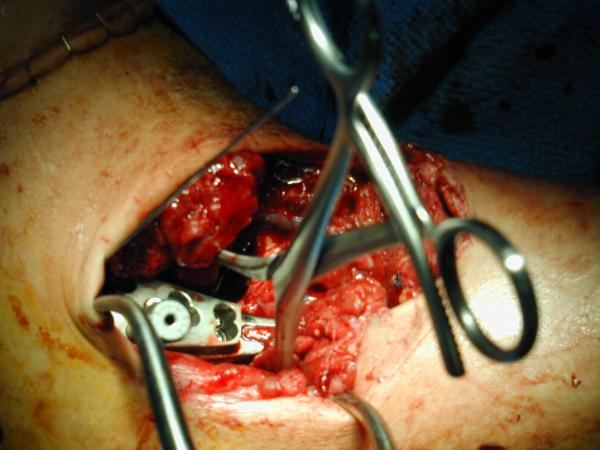

I would consider using the Synthes Proximal Humerus Locking Plate through a deltopectoral incision. After disimpacting the head you should be able to get good stabilization even in this very osteoporotic bone with the combination of converging and diverging holes. I would fill in the resulting defect with your bone volume replacement of choice. We still tend to favor autologous bone graft but have also used Norian (the semisolid putty rather than the runny liquid) and other bone graft substitutes. I will try to dig up some intraoperative and clinical photos as well as radiographs.

The attached photos show a bit of the technique.

photo 1

photo 2

photo 3

This was a 23 yo male run over by a boat with multiple propeller injuries. The fixation was carried out after several washouts with good granulation beginning and no evidence of infection. We utilized the one of the lacerations for our modified deltopectoral approach as shown in the first photo. The second photo shows the plate in place, held with a tenaculum forceps. The K-wire fits through the most superior hole in the plate with it's attached template guide. It should skim just superior to the tuberosities across the superior head and is only for positioning the plate. The third photo shows an intraoperative fluoro shot of the plate in position. The K-wire looks to be a little inferior but it may be projection. We have placed a screw through a slotted hole on the shaft to allow proximal and distal correction while maintaining rotational alignment. You can see the drill bit through the tower in one of the proximal locking holes. Sorry these aren't the greatest. I will try to dig up some better shots and some x-rays. I echo the sentiments of others that he is not likely to gain a tremendous amount of motion but we have been surprised on several occasions. From the radiographs you provided it appears that the tuberosities and, therefore, probably the rotator cuff attachments are in the ballpark although you may find it necessary to tack those down with sutures through the plate to restore the integrity of the cuff. Be prepared for the subluxation to persist for quite a while even with stabilization but it will likely improve with therapy if the cuff is attached. I have started these patients on passive, patient controlled ROM on POD #1 with flexion to 90 degrees, abduction to 70-90 degrees, and internal and external rotation to 90 degrees and neutral respectively. I'm encouraged that some recent articles have looked at comparisons between ORIF and hemiarthroplasty for Neer IIIs and IV and shown very similar results. I will send the references as soon as I am able to locate the article in my mountain of journal club articles waiting to be filed. We don't have a large series yet because the plates are relatively new (I think we were a test market) but in the dozen or so we have done we have not had any nonunions and all have had significant improvement in pain. Good luck. Warmest regards,